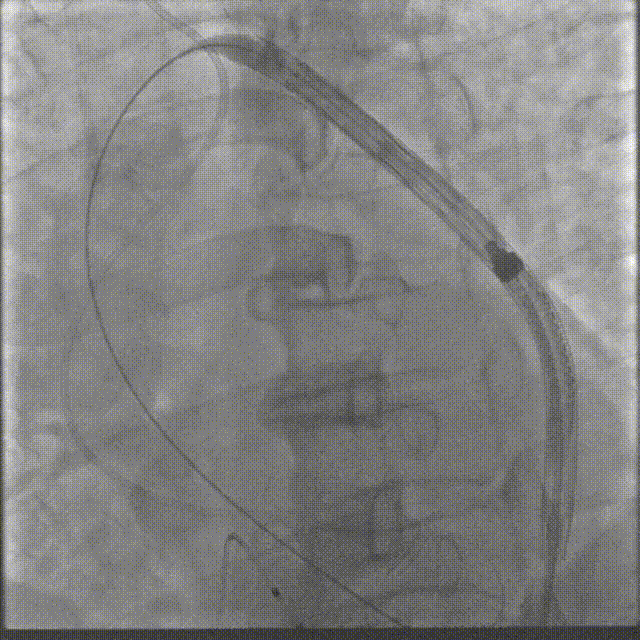

瓣膜确认位置后释放

回收极限处造影

最终造影

术后复查造影示瓣膜位置满意,形态良好,冠脉显影良好;TTE示轻微瓣周漏;排除入路血管问题,手术圆满成功。

在数字减影血管造影(DSA)与经胸超声(TTE)双模影像引导下,学员系统完成经导管主动脉瓣置换术全流程操作:首先建立经皮腹主动脉穿刺入路,随后进行导丝跨瓣定位,继而操控人工瓣膜输送系统,最终实现瓣膜精准释放。训练重点强化三个技术维度:①血管入路建立与并发症预防 ②影像引导下的器械递送路径规划 ③基于实时超声的血流动力学评估。